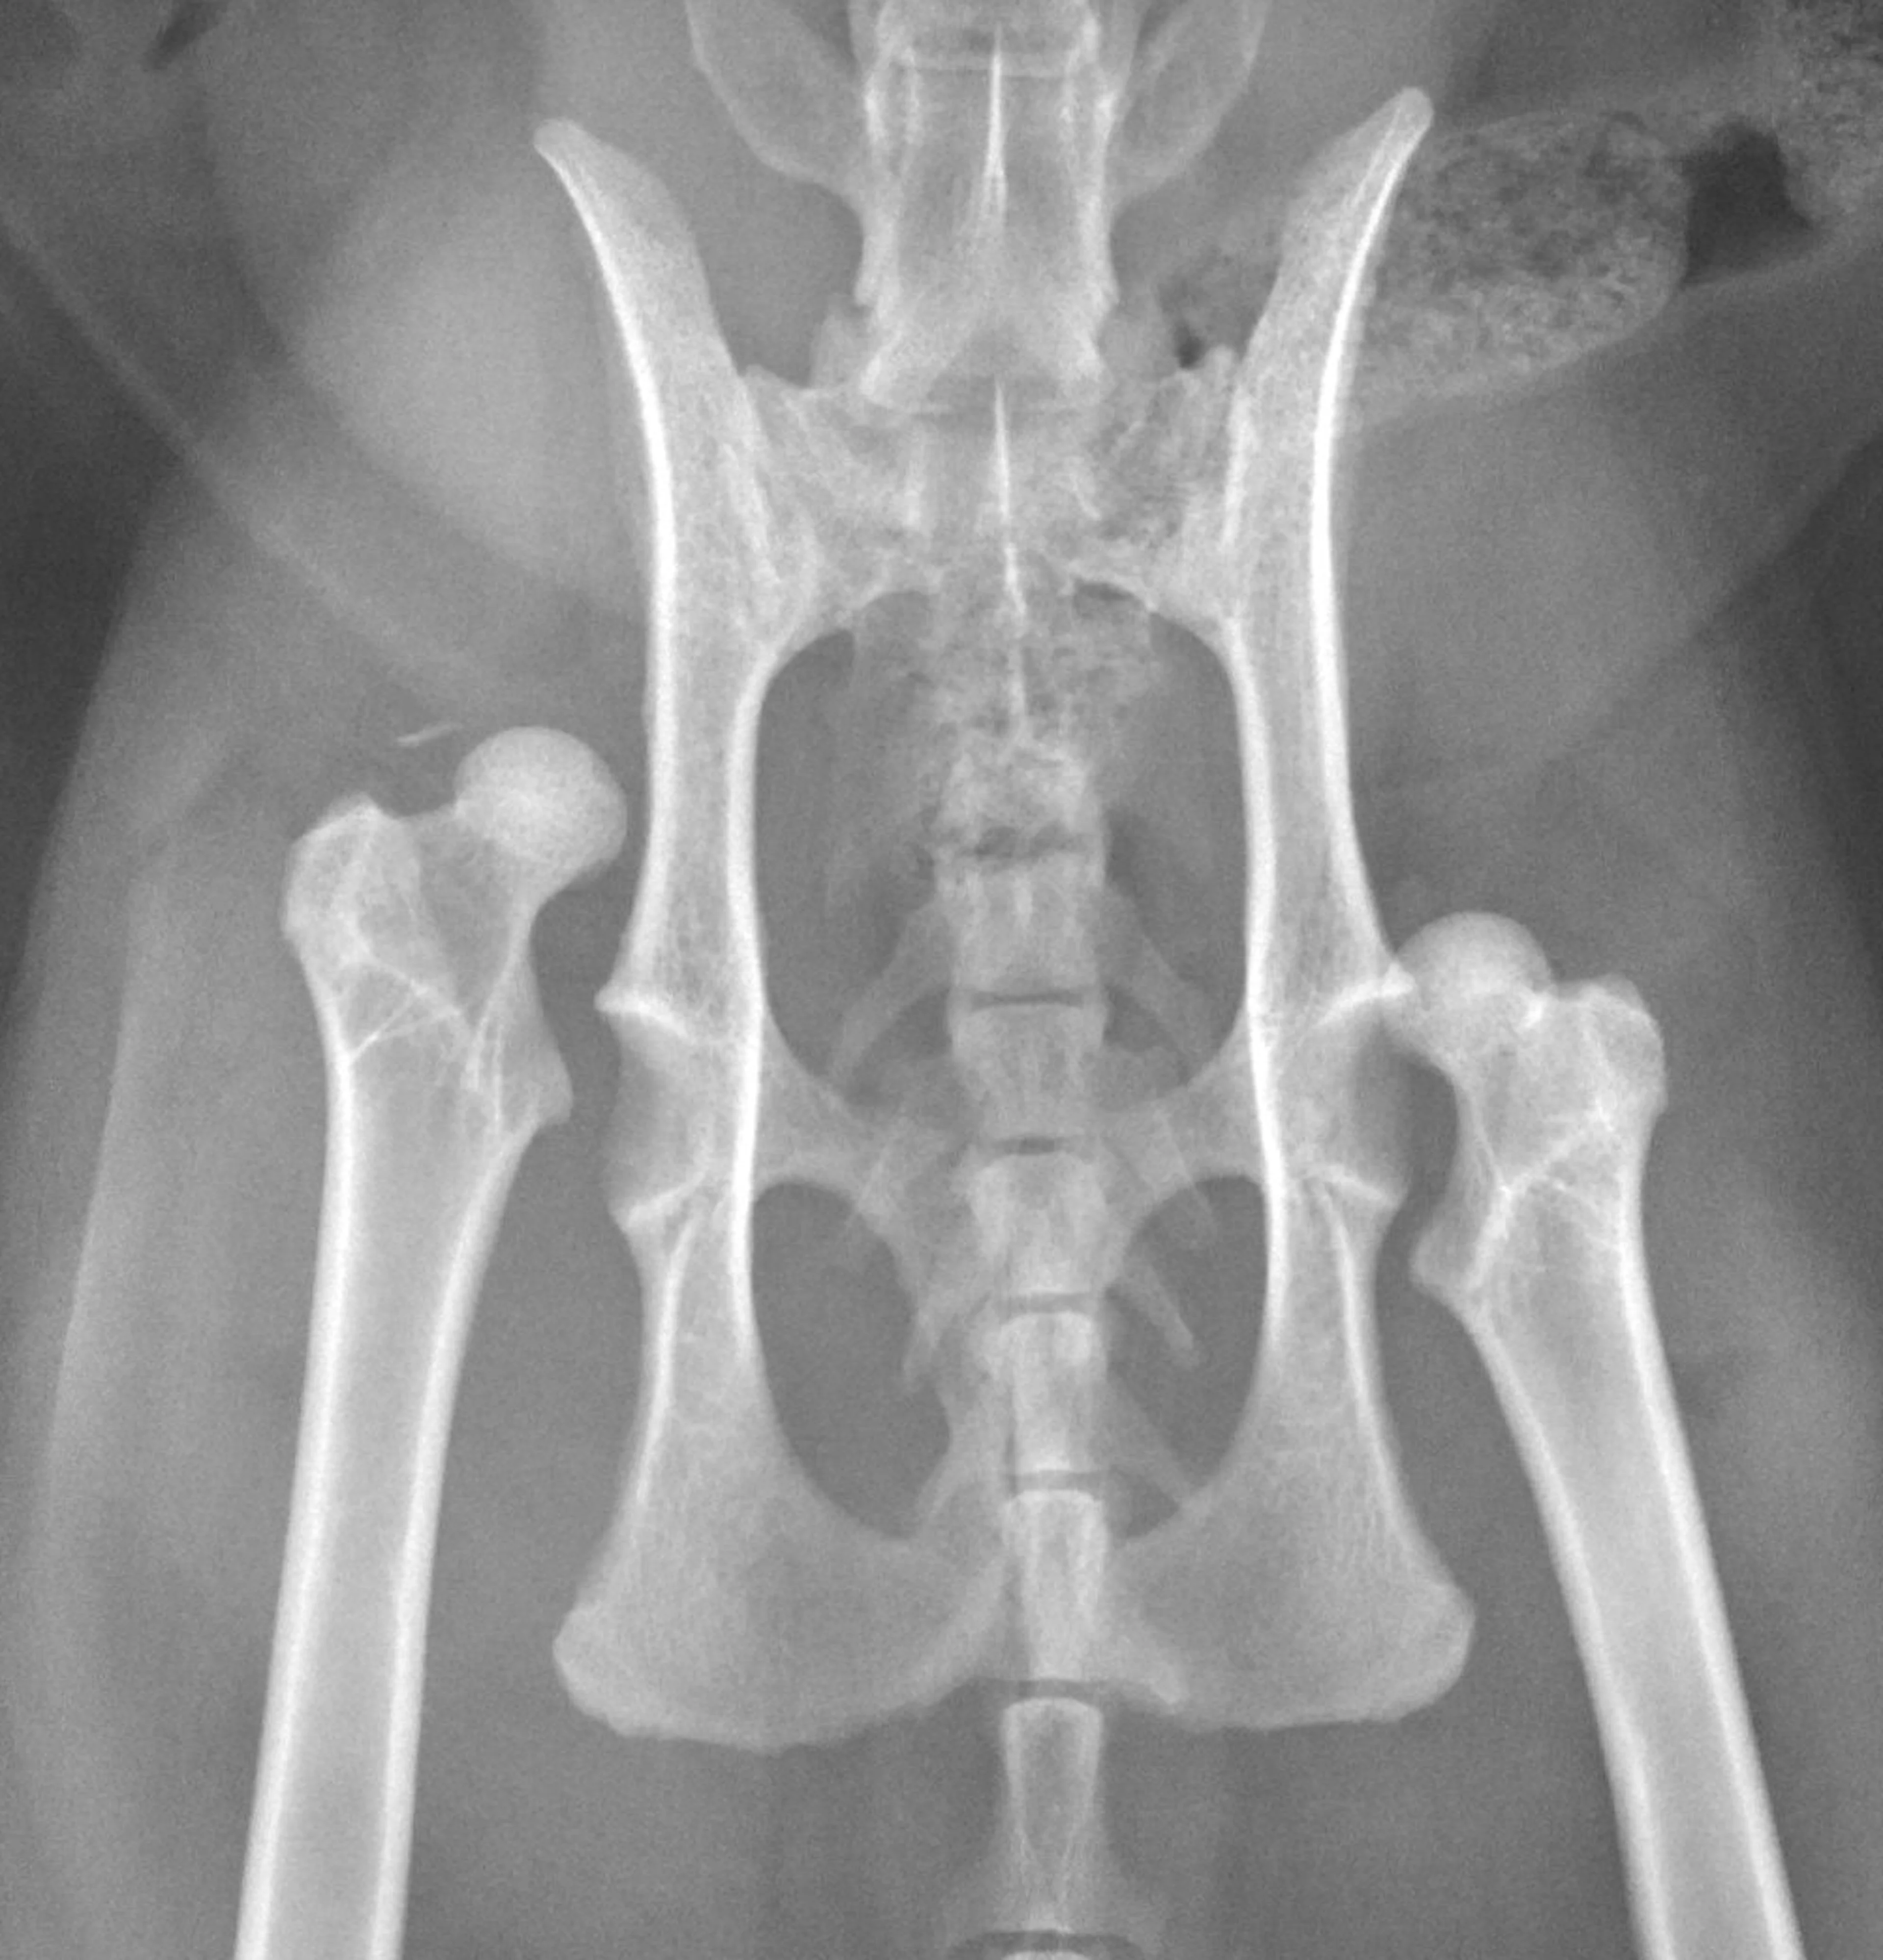

6. Surgery

Although evidence indicates primary OA is common in cats, some cases of OA may be due to treatable orthopedic conditions (eg, cranial cruciate ligament disease, hip luxation, fracture; Figure 3).2 Cats undergoing surgical treatment (eg, tibial plateau leveling osteotomy, tibial tuberosity advancement, extracapsular repair of cranial cruciate ligament tears, femoral head ostectomy, total hip replacement) for these conditions can have excellent outcomes and may have decreased OA development over time. Return to function may be faster if these conditions are addressed promptly.21-24

Bilateral hip luxation in a cat